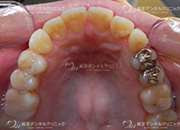

セラミックインレー

当院で扱っているセラミックインレーにはe.max(イーマックス)とジルコニアがあります。

ジルコニアインレーの方が強度がありますが、e.maxインレーの方が色が合わせやすく自然な仕上がりになる事が多いです。

ジルコニアインレーはCAD/CAMという技術により製作された物を使用し、e.max(イーマックス)はプレスいう技法で製作された物を扱っています。